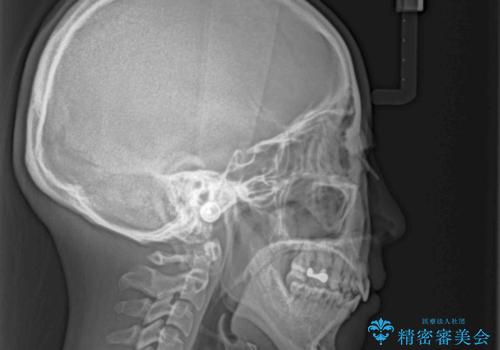

突出した口元が気になる ハーフリンガル装置による抜歯矯正

- 口元の突出感を気にして来院された患者様です。

通常では上下左右の第一小臼歯4本を抜歯しますが、下顎が左側にシフトしていたため、下顎左側のみ第二小臼歯を抜歯し、正中を合わせながら口元を下げる治療計画としました。

ハーフリンガルは、通常では表側のワイヤー矯正よりも治療期間がかかります。特に今回のように下顎左側をイレギュラーの第二小臼歯抜歯としたため、さらに時間がかかることが予想されました。

実際に治療をおこなってみると、2年を切る短期間で治療を終えることができました。